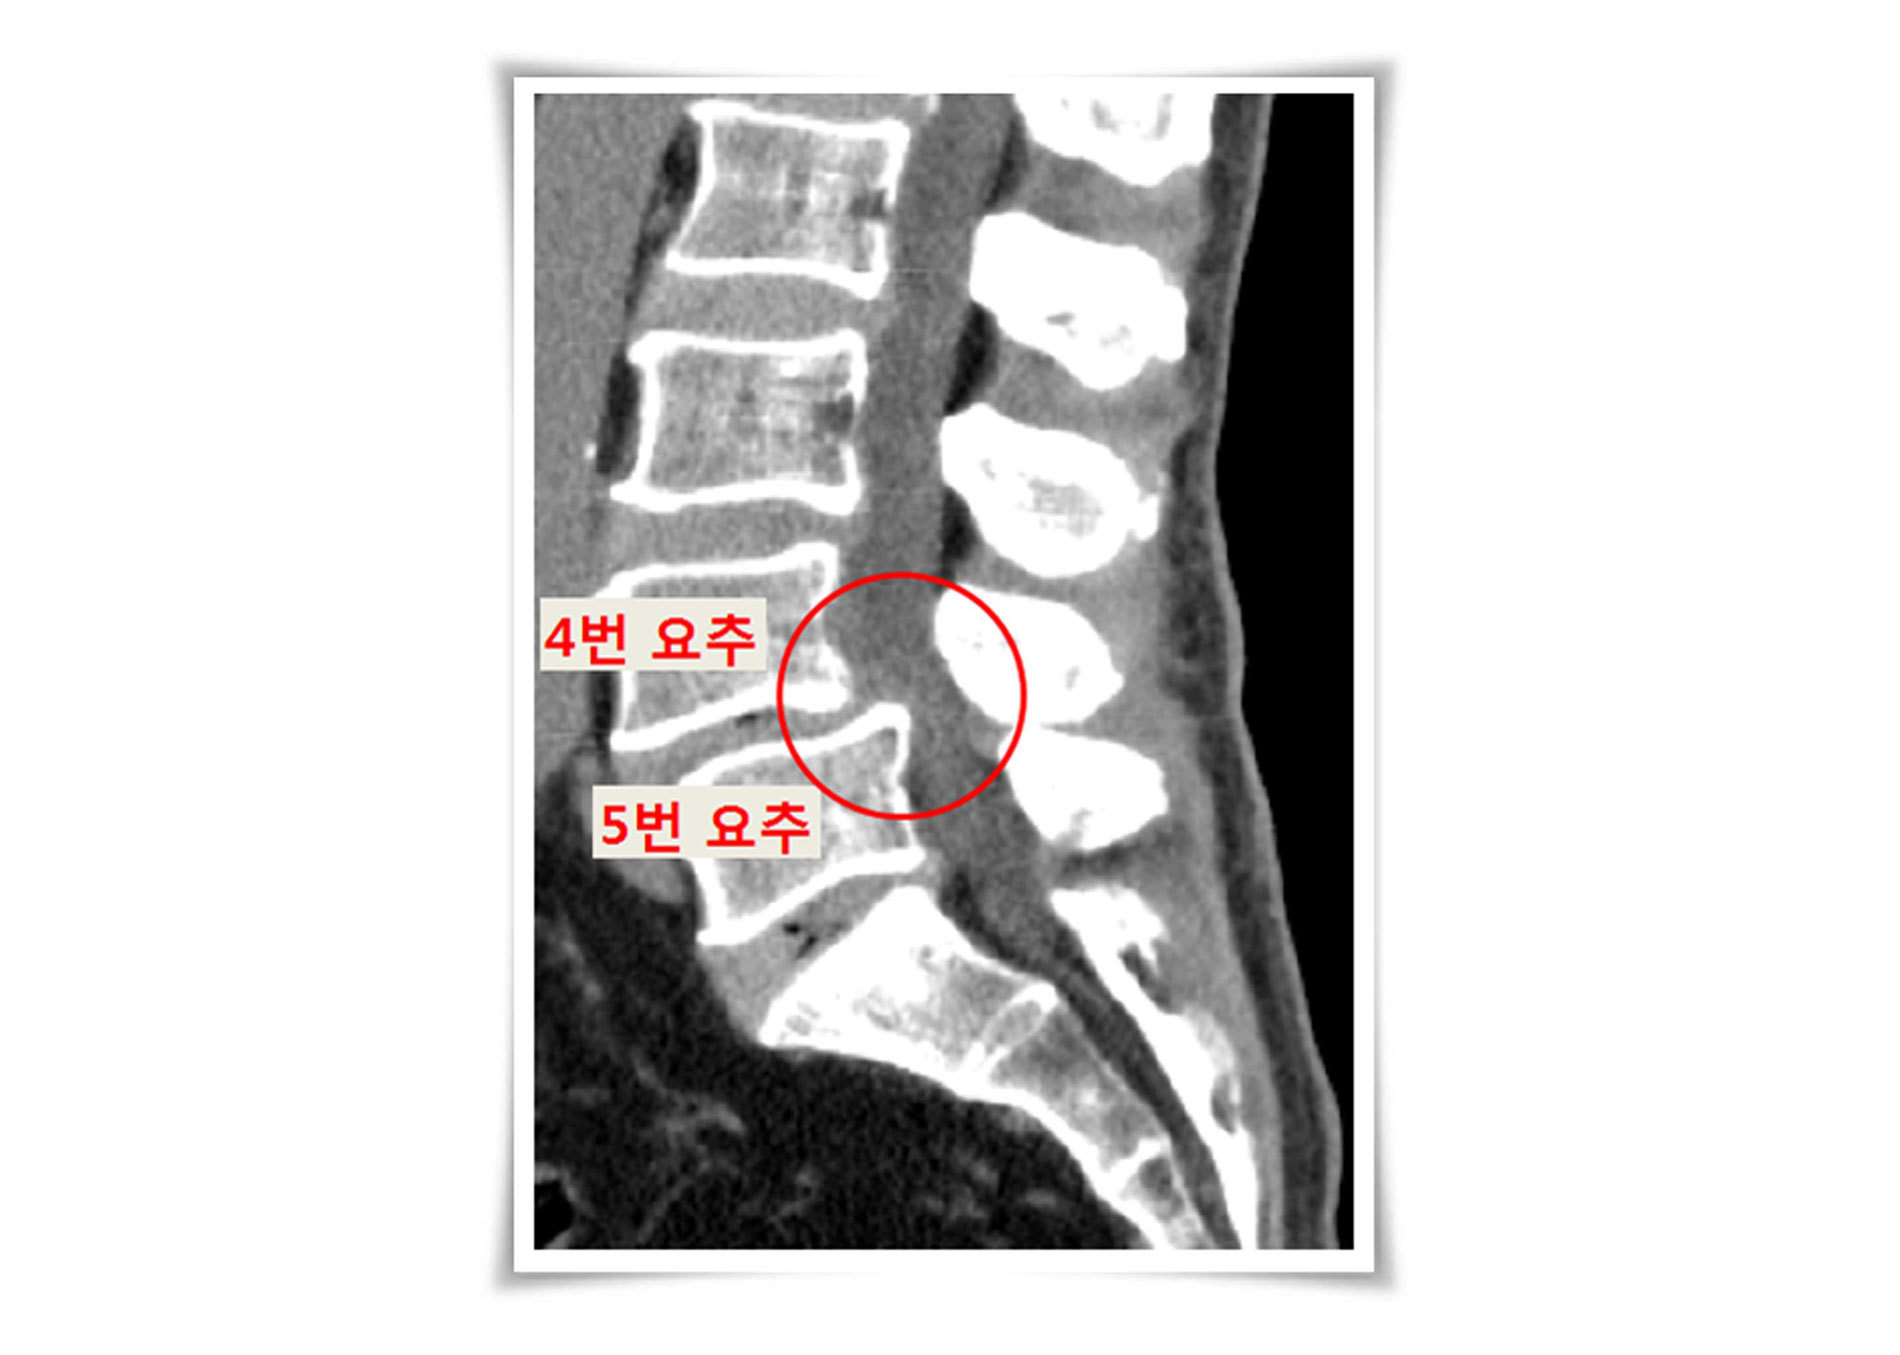

05. 척추분리증

척추뼈 뒷부분의 손상으로 서로 분리되면서 앞으로 미끄러지는 질환으로 선천적으로 발생하기도 하지만 대부분 후천성 퇴행에 의하여 발생합니다.

척추뼈가 서로 분리되면서 척수 신경과 말초 신경의 압박과 협착이 진행되면 통증과 다리의 저린감을 호소합니다.

심한 경우 수술을 고려하지만 그렇지 않다면 주사치료로 증상을 조절할 수 있습니다.